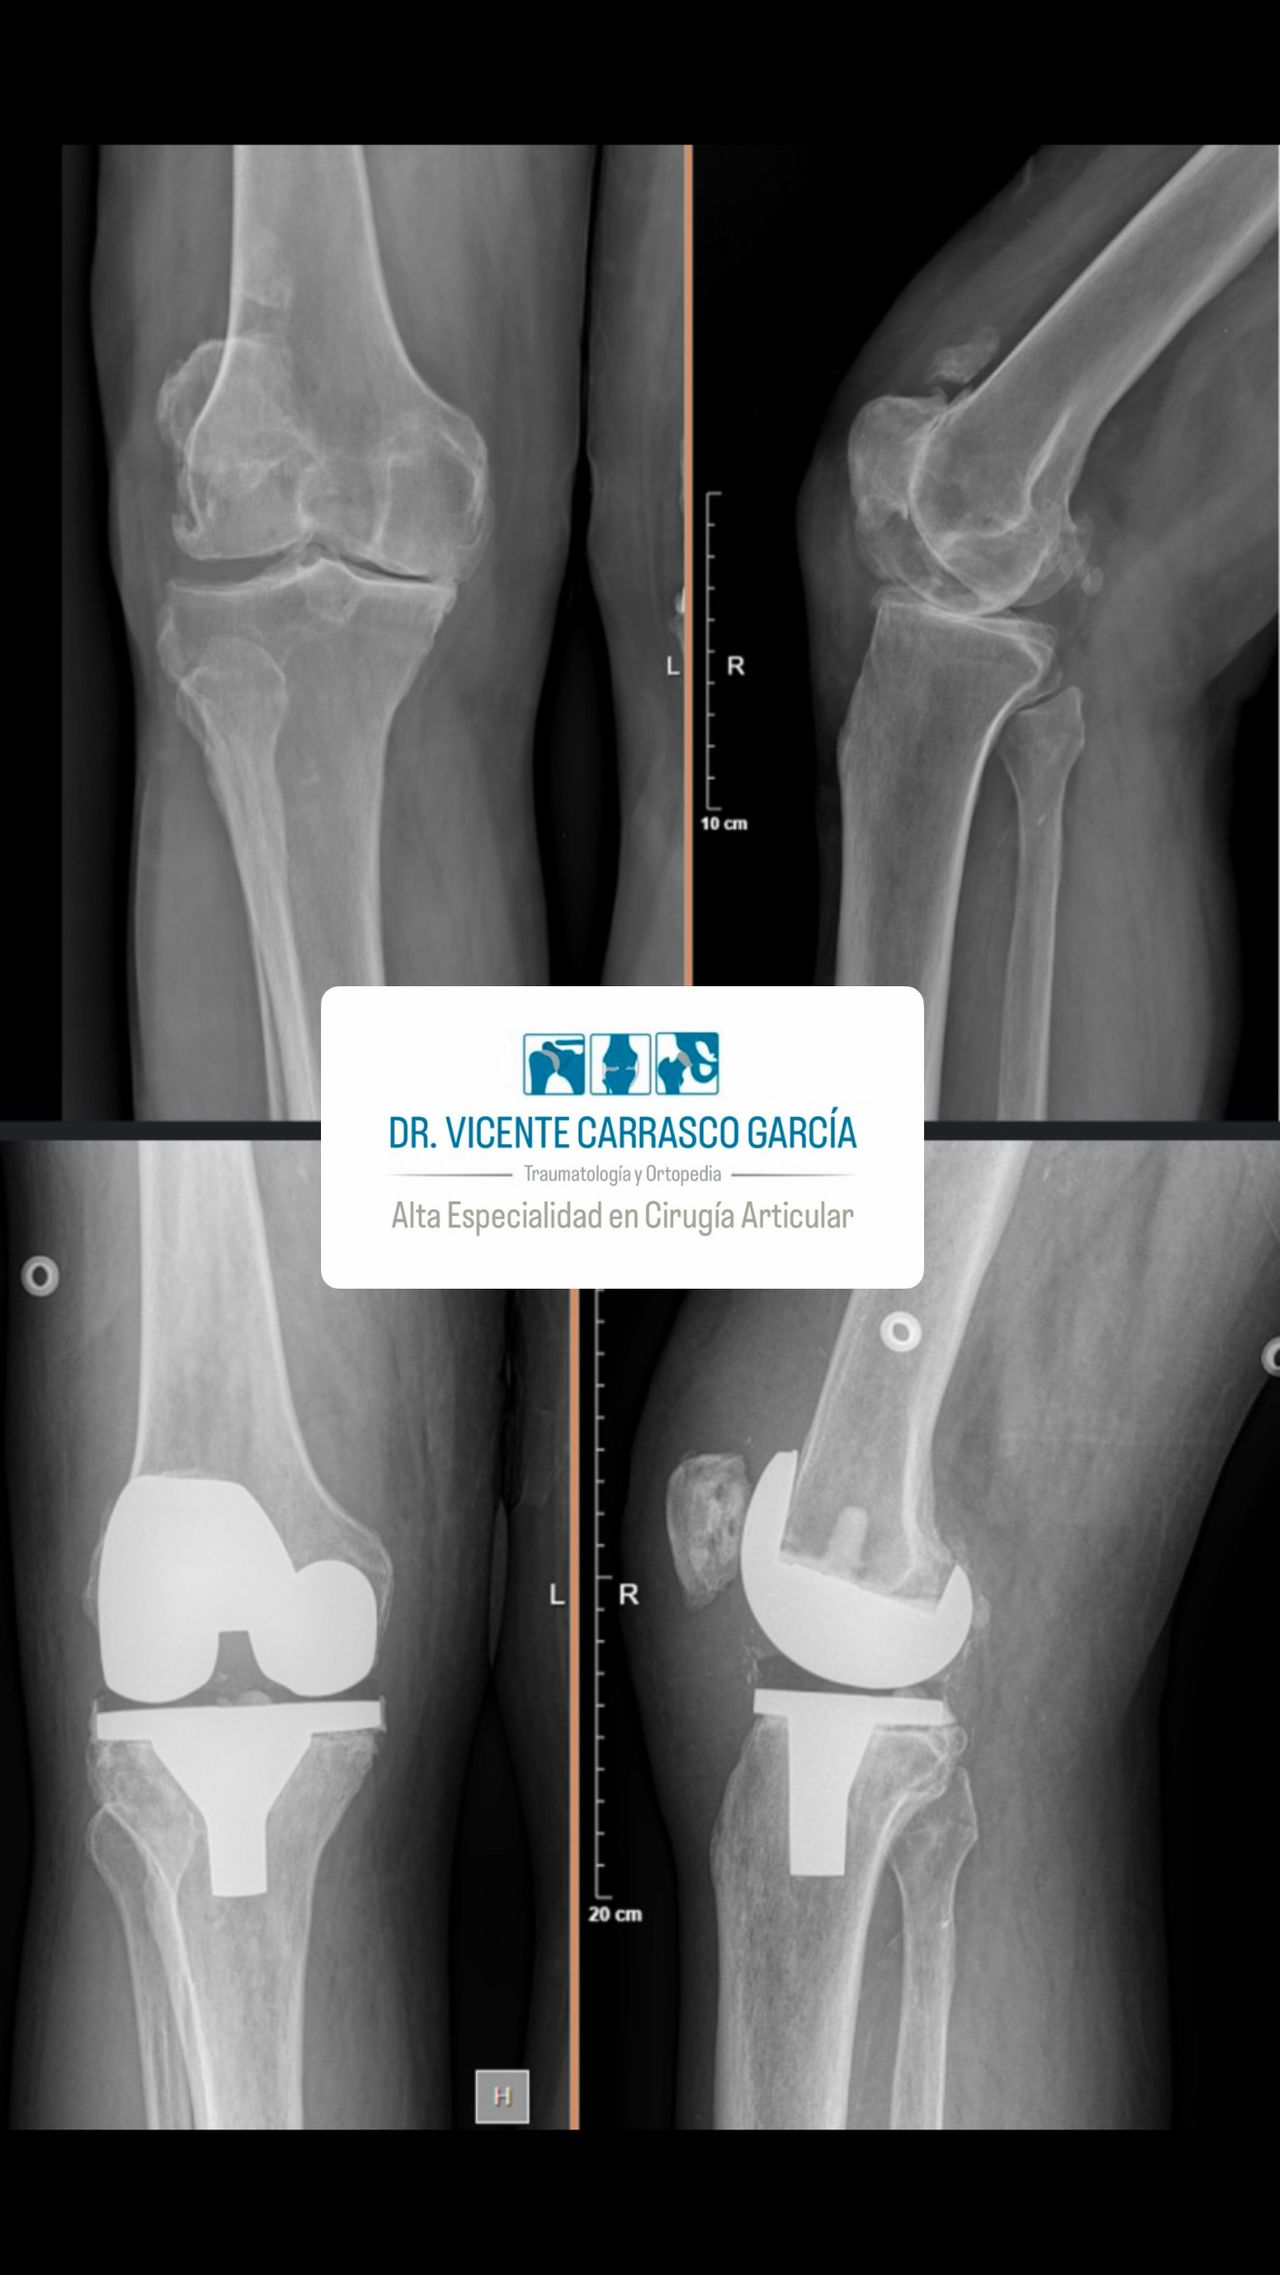

En el último año, he realizado con éxito más de 100 prótesis de rodilla y 100 prótesis de cadera, ayudando a mis pacientes a recuperar su movilidad y mejorar su calidad de vida. Mi objetivo es brindar una atención especializada y personalizada, basada en evidencia científica y en las técnicas más avanzadas disponibles en la actualidad.

• Prótesis de cadera

• Prótesis de rodilla